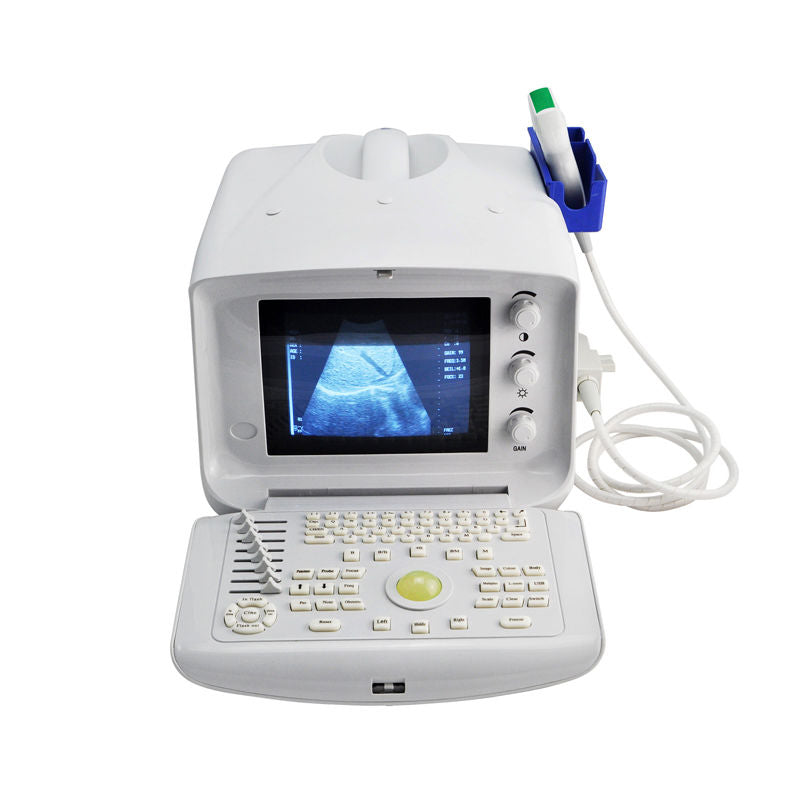

Model: RUS-6000V

Display modes: B, B+B, B+M, M, 4B

Display/ Monitor/ Screen: 10.1â high-resolution TFT LCD

Multi-frequency: Image magnification: x0.8, x1.0, x1.2, x1.5, x2.0

Pseudo color processor:7 color: Video output: PAL-D, VGA . USB port

Optional: linear/transvaginal/micro-cardiac/rectal/printer